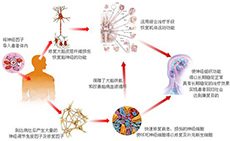

特发性血小板减少性紫癜

疾病介绍:特发性血小板减少性紫癜(ITP)亦称原发性或免疫性血小板减少性紫癜,其特点是外周血小板显著减少,骨髓巨核细胞发育成熟障碍,临床以皮肤黏膜或内脏出…【详细】